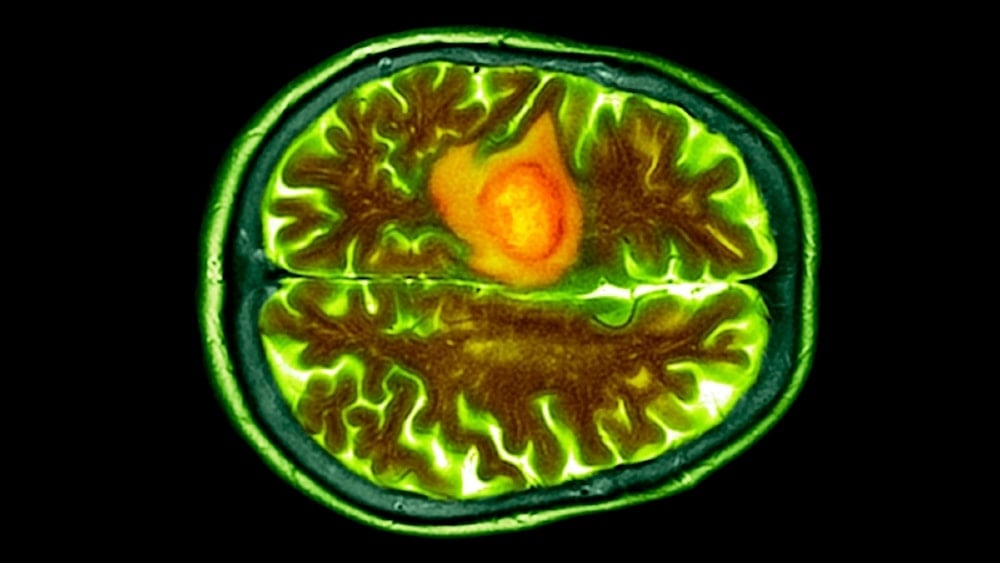

تصوير مقطعي محوسب ملون لورم أرومي دبقي في دماغ مريض. (د. ب. مارازي الصور العلمية جيتي)